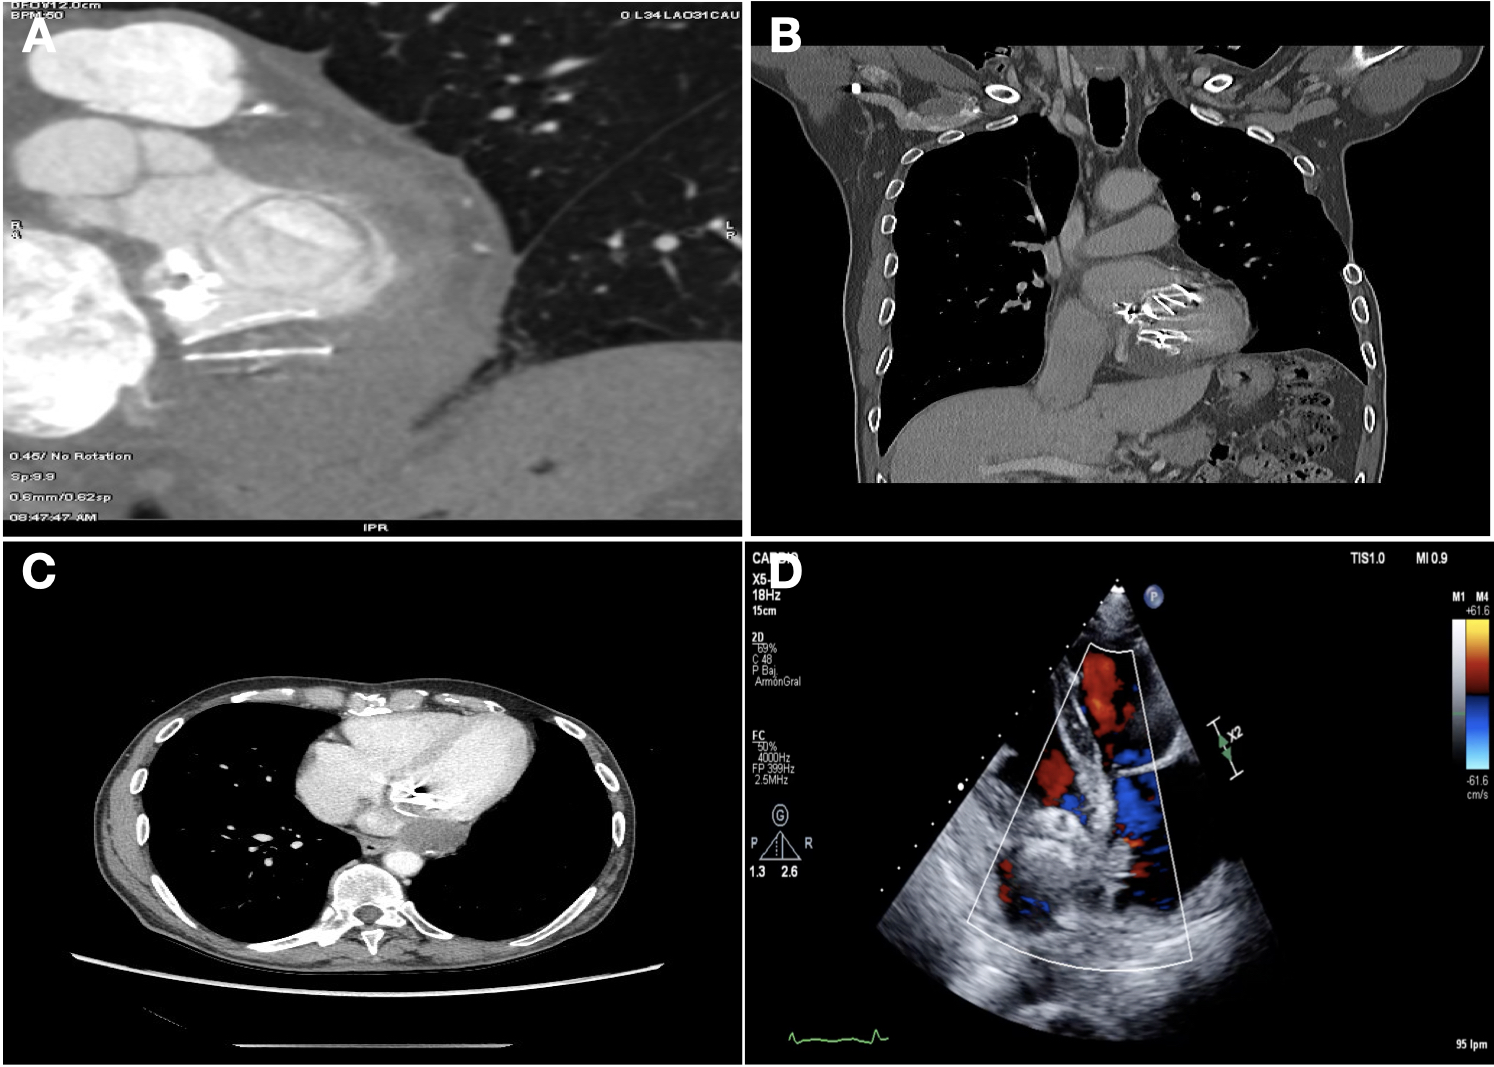

The authors present a 70-year-old man with rheumatic mitral valve disease who had undergone 3 previous open-heart surgeries, the last of which was a new mitral valve replacement for a mechanical prosthesis due to early bioprosthetic...